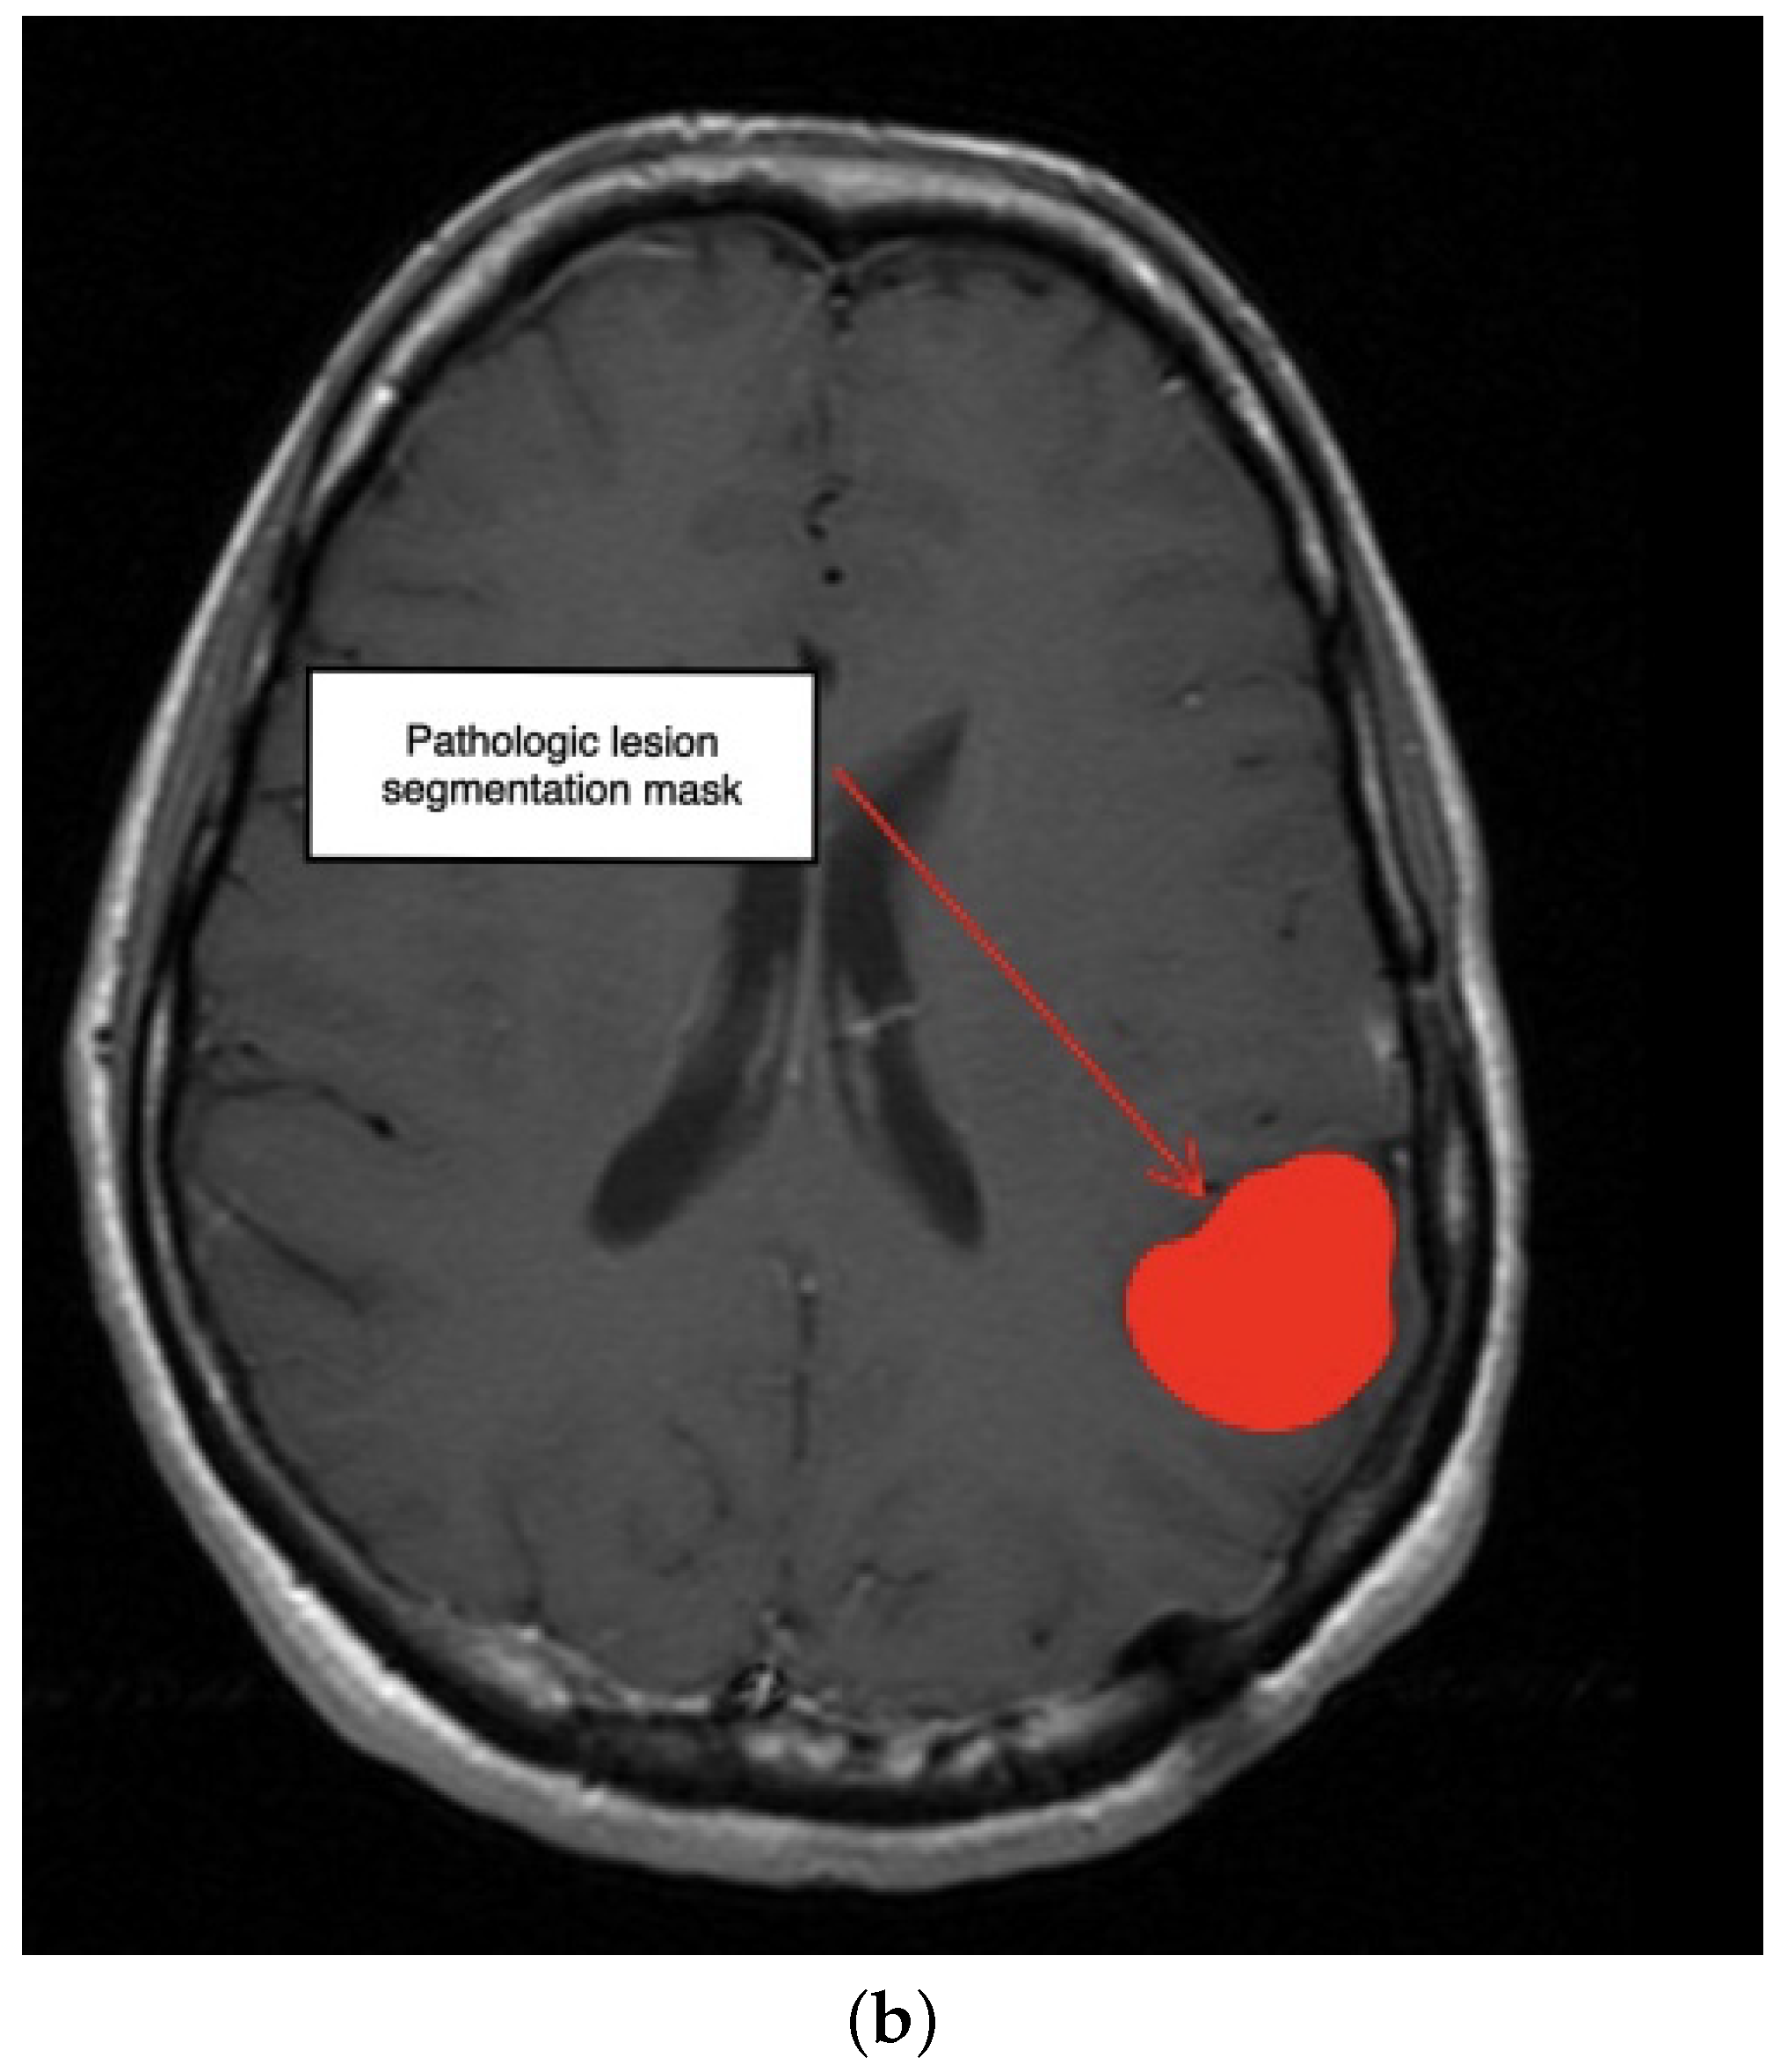

3.1. First Scenario

3.2. Second Scenario

3.3. Third Scenario